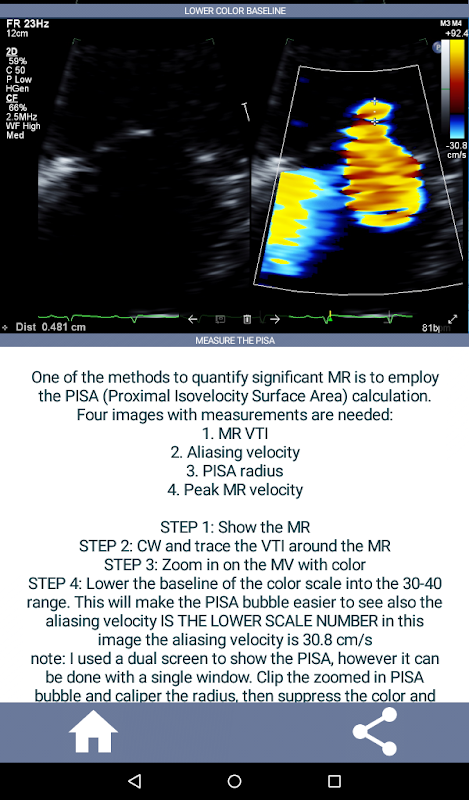

Learn the full echo ultrasound protocol that meets and exceeds the IAC Standards and Guidelines for Echocardiography Accreditation. Just starting to learn echocardiography or need a quick refresher for that echo job interview? This app will quickly get you up speed on the full TTE (transthoracic echocardiogram) protocol currently used in a major hospital from a practicing echo technologist's point of view while also providing the starting cardiac sonographer with a concise, detailed "how to" guideline on a complete echo exam. The app consists of over 90% video clips displaying proper views and also showing the most common abnormal cardiac pathology (e.g. aortic stenosis) that an echo tech will likely encounter and what to do.

• STEP BY STEP VIDEO CLIPS SHOWING THE ENTIRE ECHO PROTOCOL

• ADDITIONAL INFORMATION/EXAMPLE PAGES SHOWING ABNORMAL PATHOLOGY (E.G. AORTIC DISSECTION) ALLOWING EASY COMPARISON OF NORMAL VS ABNORMAL